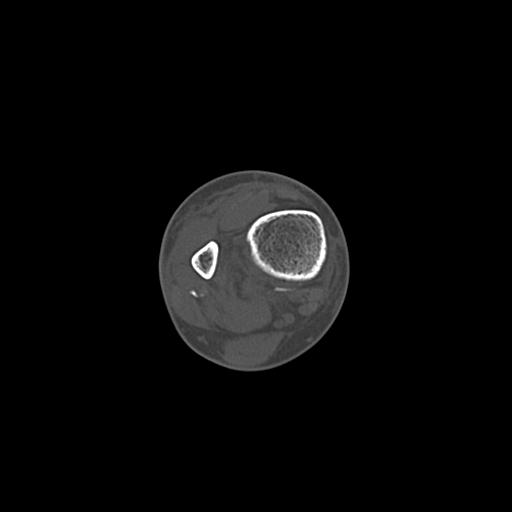

110211 1/6 1/8 左前腕 4R 15歳男性 橈骨骨幹部骨折